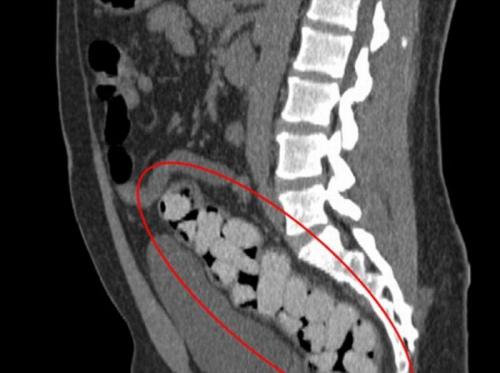

Наркотики в толстой кишке.